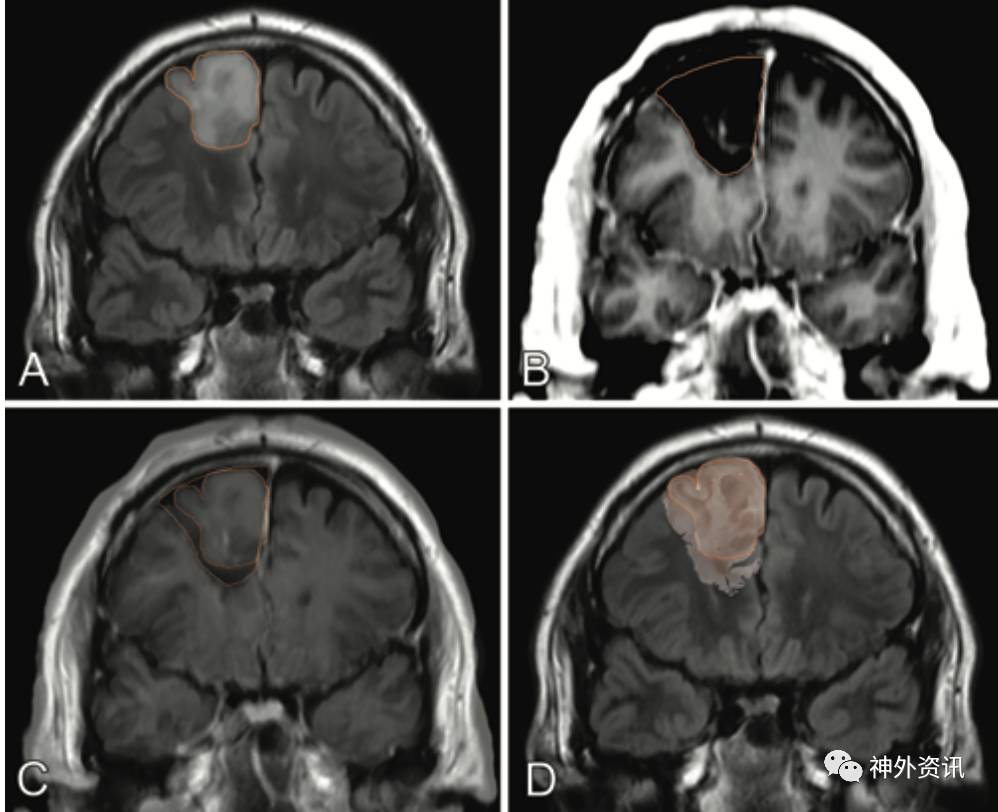

图1. 病例1患者的影像学资料。A.术前MRI冠状位T2-FLAIR成像勾画的肿瘤边界;B.术后MRI冠状位T1勾画的瘤腔边界;C.手术前、后MRI冠状位影像叠加图,可显示切除的肿瘤周边组织;D.IDH1染色图片与MGI冠状位T2-FLAIR图像叠加图。